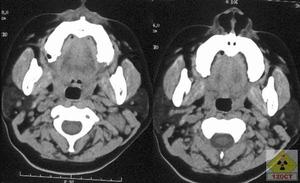

鼻咽癌為鼻咽部最常見的惡性腫瘤,好發於頂壁和頂後壁,發生於咽隱窩者早期表現為咽隱窩變淺或消失,另一個重要的表現為咽肌的增厚和不對稱。腫瘤向外侵犯可致咽旁間隙變窄、移位、甚或閉塞;向上延伸可侵及顱底、海綿竇或腦內,引起顱底骨質結構破壞或伴硬化。腫瘤還常向下侵犯累及口咽部使口咽側壁軟組織增厚。頸部淋巴結轉移較常見,多為同側或雙側性,少數以對側淋巴結明顯。